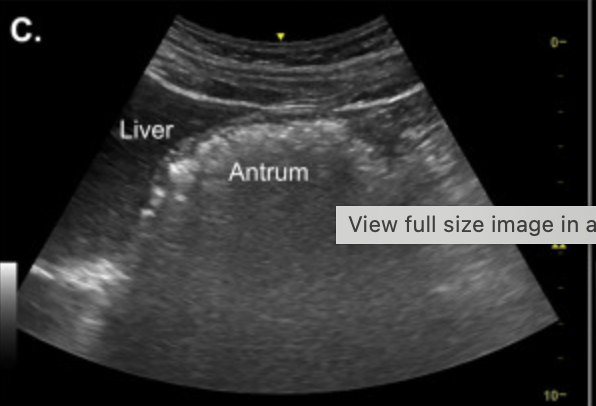

Gastric US image

a) Fluid less than 100

b) Fluid over 100ml

c) Late stage solid

d) Early stage solid

A

Early Solid stage